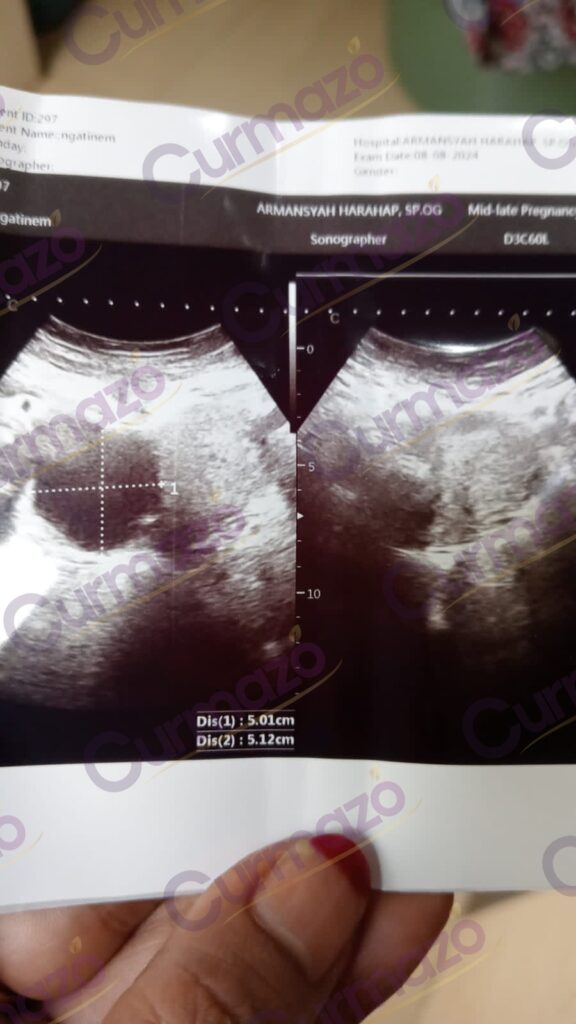

Foto hasil USG before:

Karena ukuran kistanya sudah besar jadi dokter menyarankan untuk dioperasi. Saya dengar kata operasi aja sudah parno duluan. Takut banget kalau sampai dioperasi, jadi saya cari pengobatan kista selain operasi di Facebook, keluar rekomendasi herbal Curmazo dan K-Muricata. Setelah baca-baca testi sudah banyak yang bisa pulih, saat itu juga saya langsung konsultasi dan pesan 1 paket.